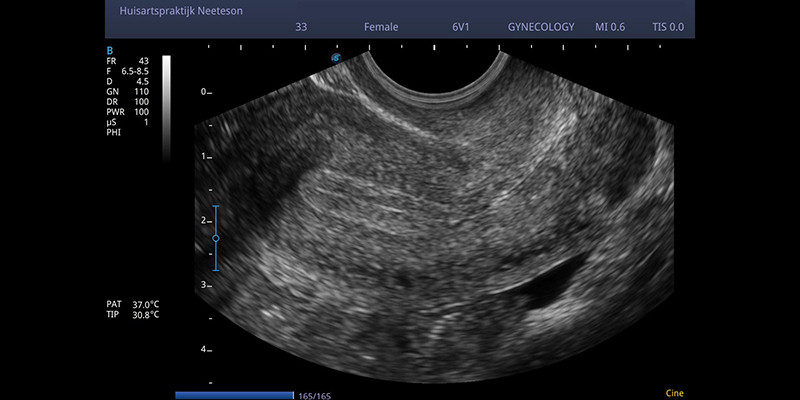

Dit artikel beschrijft een horizontaal verwijsproject van een regionale zorggroep met 165.000 patiënten, waarin huisartsen konden verwijzen naar een kaderhuisarts voor transvaginale gynaecologische echografie. In de jaren 2019-2021 maakte deze kaderhuisarts 481 echo’s. De meest gestelde diagnose was ‘geen afwijkingen’ (56%); er werden geen ernstige diagnoses gemist. Dergelijke horizontale verwijzingen lijken veelbelovend: ze zijn laagdrempeliger, goedkoper en de wachttijden zijn korter.